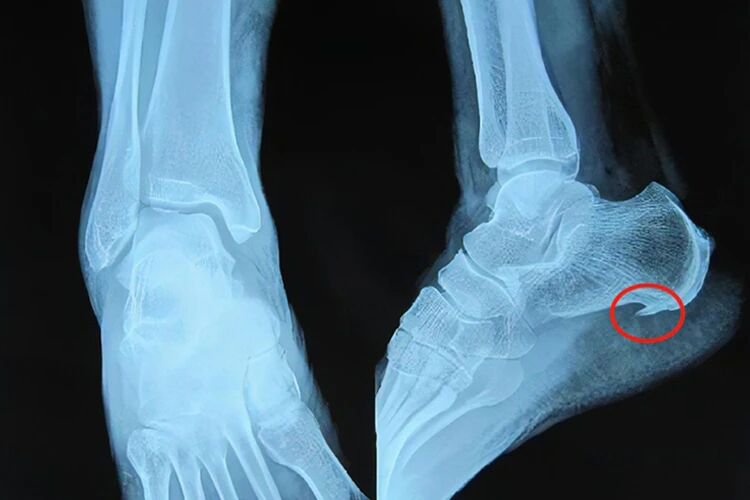

3、足跟骨质增生

即“足跟骨刺”,当足跟关节出现磨损、破坏后,人体会进行自我修复、硬化与增生,从而形成足跟骨刺,是一种自然的老化现象。

高发人群high-risk group

45岁以上的中老年人群

体重超标的肥胖症人群

治疗方案treatment plan

一般治疗:口服非类固醇抗炎药或进行封闭止痛

针刀治疗:松解软组织粘连和痉挛,减轻骨刺压迫,缓解疼痛并改善足跟的功能

手术治疗:利用手术方式切除增生的骨刺